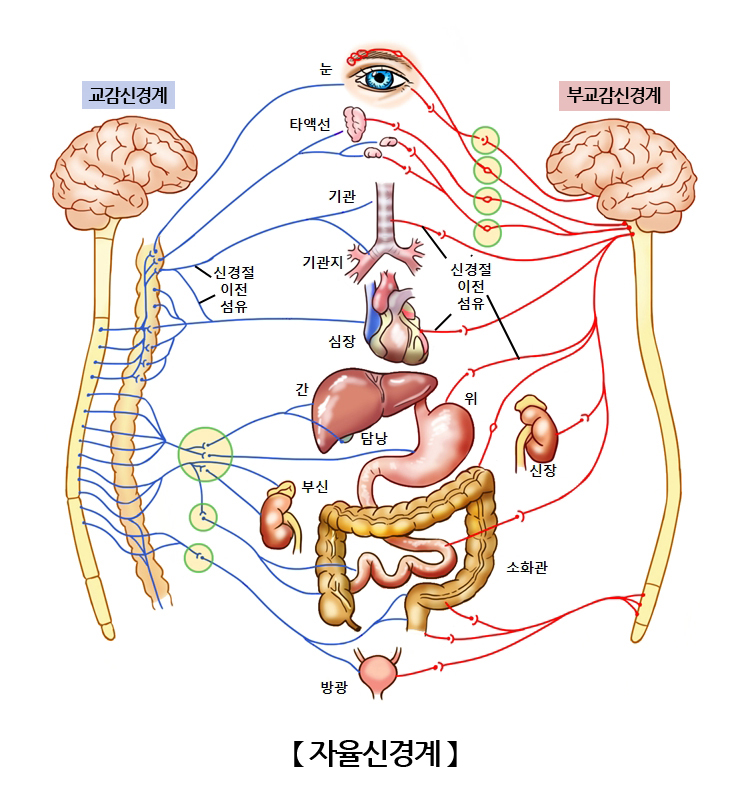

말초신경계통에 속하는 신경계로 우리 몸 속의 장기와 심장, 외분비샘, 내분비샘을 통제하여 우리 몸의 환경을 일정하게 유지하는 역할을 합니다. 자율신경계는 교감신경과 부교감신경으로 나눌 수 있습니다. 교감신경은 위급한 상황에 빠졌을 경우 빠르게 대처할 수 있도록 도와주는 역할을 하며 부교감신경은 위급한 상황에 대비하여 에너지를 저장해두는 역할을 합니다.

말초신경계는 중추신경계 안에 있는 절전신경세포와 중추신경계 밖에 있는 절후신경세포로 나뉘어집니다. 교감신경의 절전신경세포는 흉추 1번에서 요추 2번까지 위치하며 부교감신경의 절전신경세포는 천추2번~4번에 위치합니다. 이 절전신경세포는 여러개의 절후신경세포와 연결되어 신체 여러 부위의 기능을 조절하게 됩니다. 교감신경은 절전신경의 길이가 짧고 부교감 신경은 절후신경의 길이가 짧습니다. 교감신경절후신경세포에서 분비되는 신경전달물질은 노르에피네프린이며 부교감신경절후신경세포에서 분비되는 신경전달물질은 아세틸콜린입니다.

교감신경과 부교감신경은 서로 반대 작용을 하면서 우리 몸의 환경을 일정하게 유지하는 역할을 합니다.

교감 신경

척수의 중간 부분에서 나와 여러 내장기관에 분포하며 위급한 상황에 빠졌을 경우 빠르게 대처할 수 있도록 도와주는 역할을 합니다. 교감신경 흥분 시 동공은 확장되고 땀의 분비가 촉진되며 심장박동수가 증가하고 혈관은 수축합니다. 또한 기관지가 확장되며 위장관 운동은 저하됩니다.

부교감 신경

중뇌와 연수 및 척수의 꼬리부분에서 나와 각 내장기관에 분포하며 위급한 상황에 대비하여 에너지를 저장해두는 역할을 합니다. 부교감신경 흥분 시 동공은 수축하고 땀 분비는 감소하며 심박동수는 감소하고 일부 혈관이 확장될 수 있습니다. 또한 기관지는 수축하며 위장관 운동이 촉진됩니다.